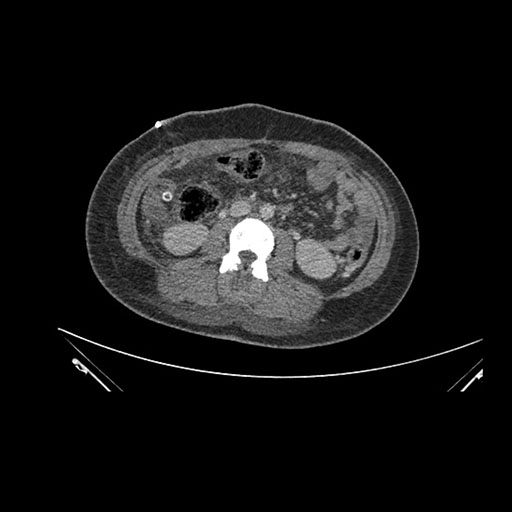

Axial Venous